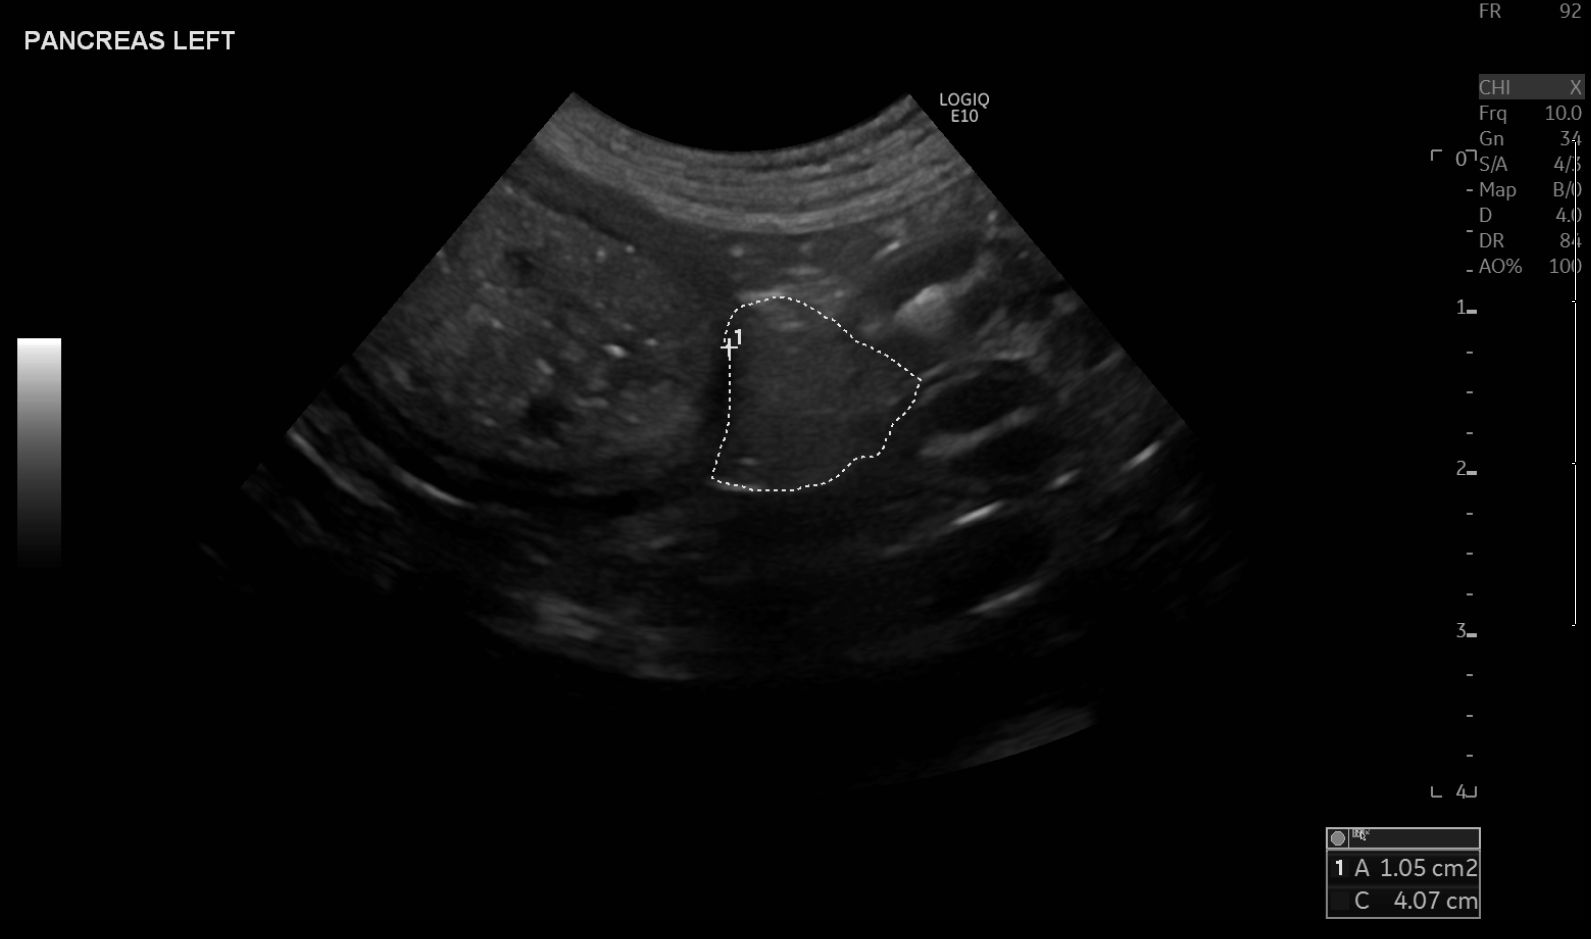

Bildgebende Diagnostik von endokrinen Organen in der Kleintierpraxis – Teil 2: Hypophyse, Nebennieren und Pankreas

Die Bildgebung ist ein wichtiger Bestandteil der Diagnostik endokriner Erkrankungen bei Kleintieren. Die Wahl der Bildgebungsmodalität richtet sich nach dem betroffenen Organsystem, der technischen Ausstattung und der klinischen Fragestellung. Röntgen, Ultraschall, CT und MRT ermöglichen die Beurteilung von Hypophyse, Nebennieren und Pankreas. Während Ultraschallmerkmale von Nebennierenläsionen keine eindeutige Unterscheidung zwischen benignen und malignen Prozessen erlauben, liefern CT und MRT erweiterte Informationen, insbesondere bei der Abklärung des Cushing-Syndroms und von Tumoren. Verschiedene endokrinologische Erkrankungen können Veränderungen in mehreren Organsystemen hervorrufen, weshalb eine Kombination aus Bildgebung, klinischen Befunden und Laborwerten für die Diagnose und Verlaufskontrolle unerlässlich ist.

Imaging diagnostics play an important role in the identification and differentiation of endocrine diseases in dogs and cats. This article provides a practical overview of the use and diagnostic value of X-ray, ultrasound, CT, and MRI for assessing the pituitary gland, adrenal glands, and pancreas. Typical findings, such as adrenal size measurement or tumor visualization, are discussed. The limitations of each imaging modality, such as the restricted ability of ultrasound to distinguish between benign and malignant changes, are also critically examined. Ultimately, imaging findings must always be interpreted in the context of clinical symptoms as well as laboratory and pathological results for a definitive diagnosis.